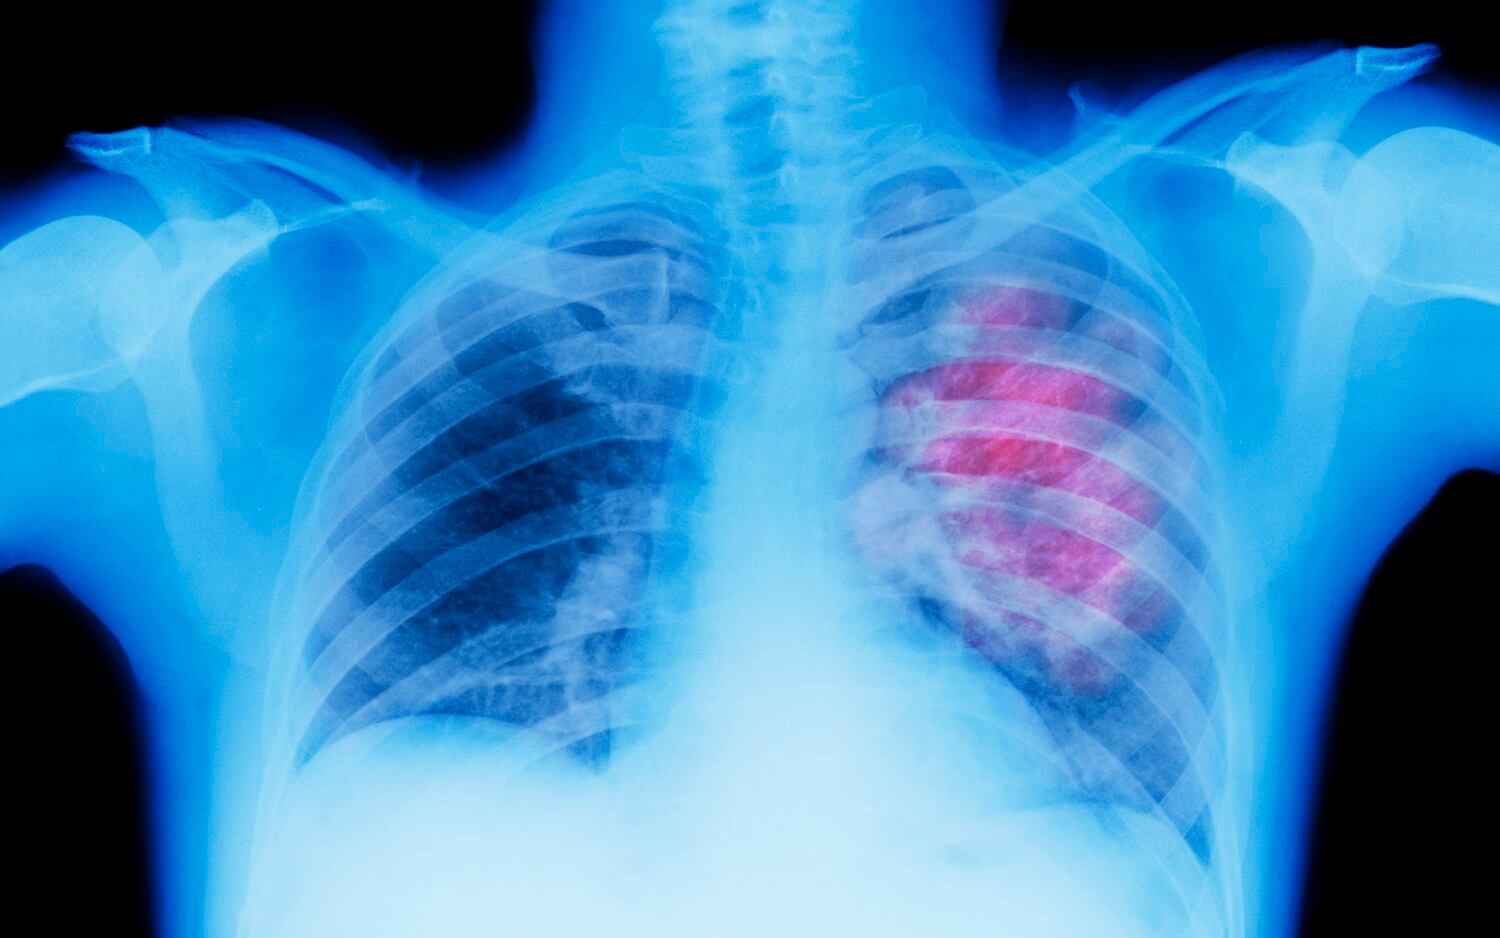

“El cáncer de pulmón es un cáncer que se forma en los tejidos del pulmón, generalmente en las células que recubren los conductos de aire. Es la principal causa de muerte por cáncer tanto en hombres como mujeres. Hay dos tipos principales, cáncer de pulmón de células pequeñas y cáncer de pulmón de células no pequeñas. Estos dos tipos crecen de manera diferente y se tratan de manera diferente”, explica MedlinePlus, Biblioteca Nacional de Medicina de los Estados Unidos.

Las personas que están expuestas a padecer una enfermedad como el cáncer de pulmón son aquellas que fuman, las que están expuestas a humos de segunda mano, las que tienen familiares que sufrieron este trastorno y las que se exponen a la radiación.

Por último, es de resaltar que otros de los síntomas que genera el cáncer de pulmón son los dolores o molestias en el pecho, la tos que no desparece, la dificultad para respirar, las sibilancias, la ronquera, la pérdida de apetito, la fatiga y la inflamación en el rostro.